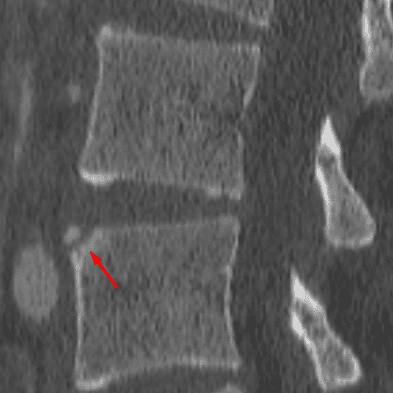

Limbus Vertebra

Case 9